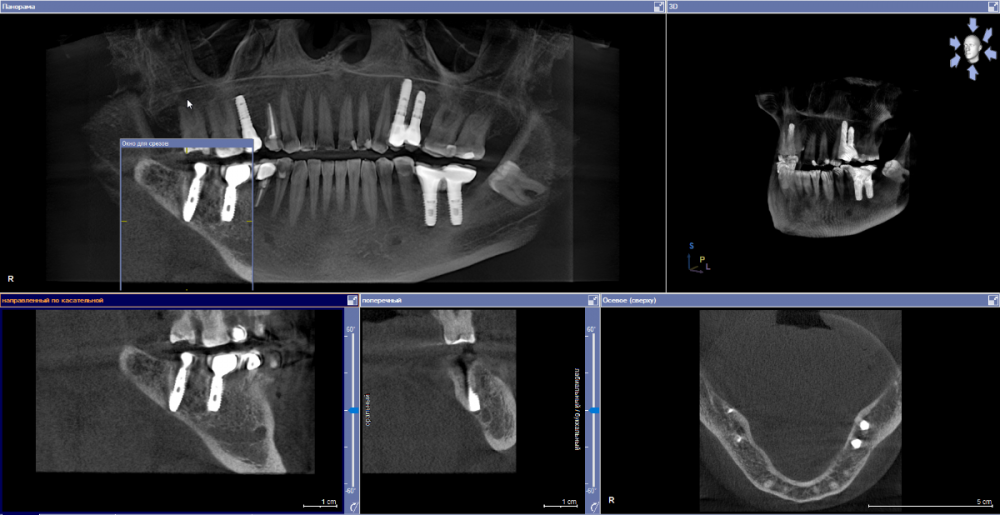

se77777 Опубликовано 3 апреля, 2023 Автор Поделиться Опубликовано 3 апреля, 2023 Здравствуйте, проведена одномоментная имплантация. Спустя 5 месяцев поставлена коронка. Коронка стоит месяц. На третьем месяце после имплантации стала беспокоить боль в плече, списывал на перенесенный COVID-19. Было субъективное ощущение, что температура формирователя повышена по отношению к остальным зубам и к формирователям, которые носил прежде. На днях стали беспокоить тянущая неинтенсивная боль в челюсти со стороны импланта. КТ сделана полтора месяца назад. Ссылка на комментарий

red_butler Опубликовано 3 апреля, 2023 Поделиться Опубликовано 3 апреля, 2023 Здравствуйте, срезы кт выставлены не правильно. Покажите еще Ссылка на комментарий

АнтонТЛТ Опубликовано 4 апреля, 2023 Поделиться Опубликовано 4 апреля, 2023 У нижних двух окошек есть ползунки слева. Оси нужно выставить параллельно имплантату 1 Ссылка на комментарий

red_butler Опубликовано 5 апреля, 2023 Поделиться Опубликовано 5 апреля, 2023 по Кт все нормально, нужно смотреть очно 1 Ссылка на комментарий